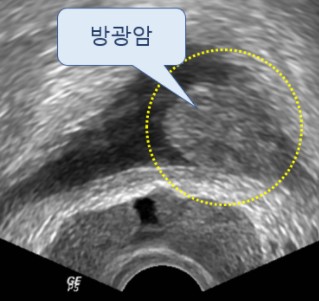

8. 혈뇨

전립선암은 혈뇨 증상도 동반할 수 있습니다. 혈뇨란 소변에서 피가 섞여서 나오는 것을 말해요. 전립선암이 요도와 방광 내로 진전되면 출혈이 발생하기 그리해서 혈뇨가 나올 수 있습니다.

9. 요실금

전립선암은 요실금 증상도 유발하게 됩니다. 요실금 증세는 자신의 의지와 무관하게 소변을 보게 되는 현상을 말해요. 암이 방광으로 전이되면서 방광 자극이 심해지면 요실금이 생긴다고 해요.